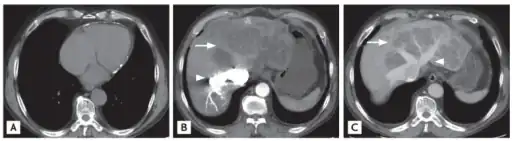

a) Sparse pericardial calcification with eccentric wall thickening b,c) liver CT shows variable regions of low attenuation, often called the “nutmeg liver” arrows